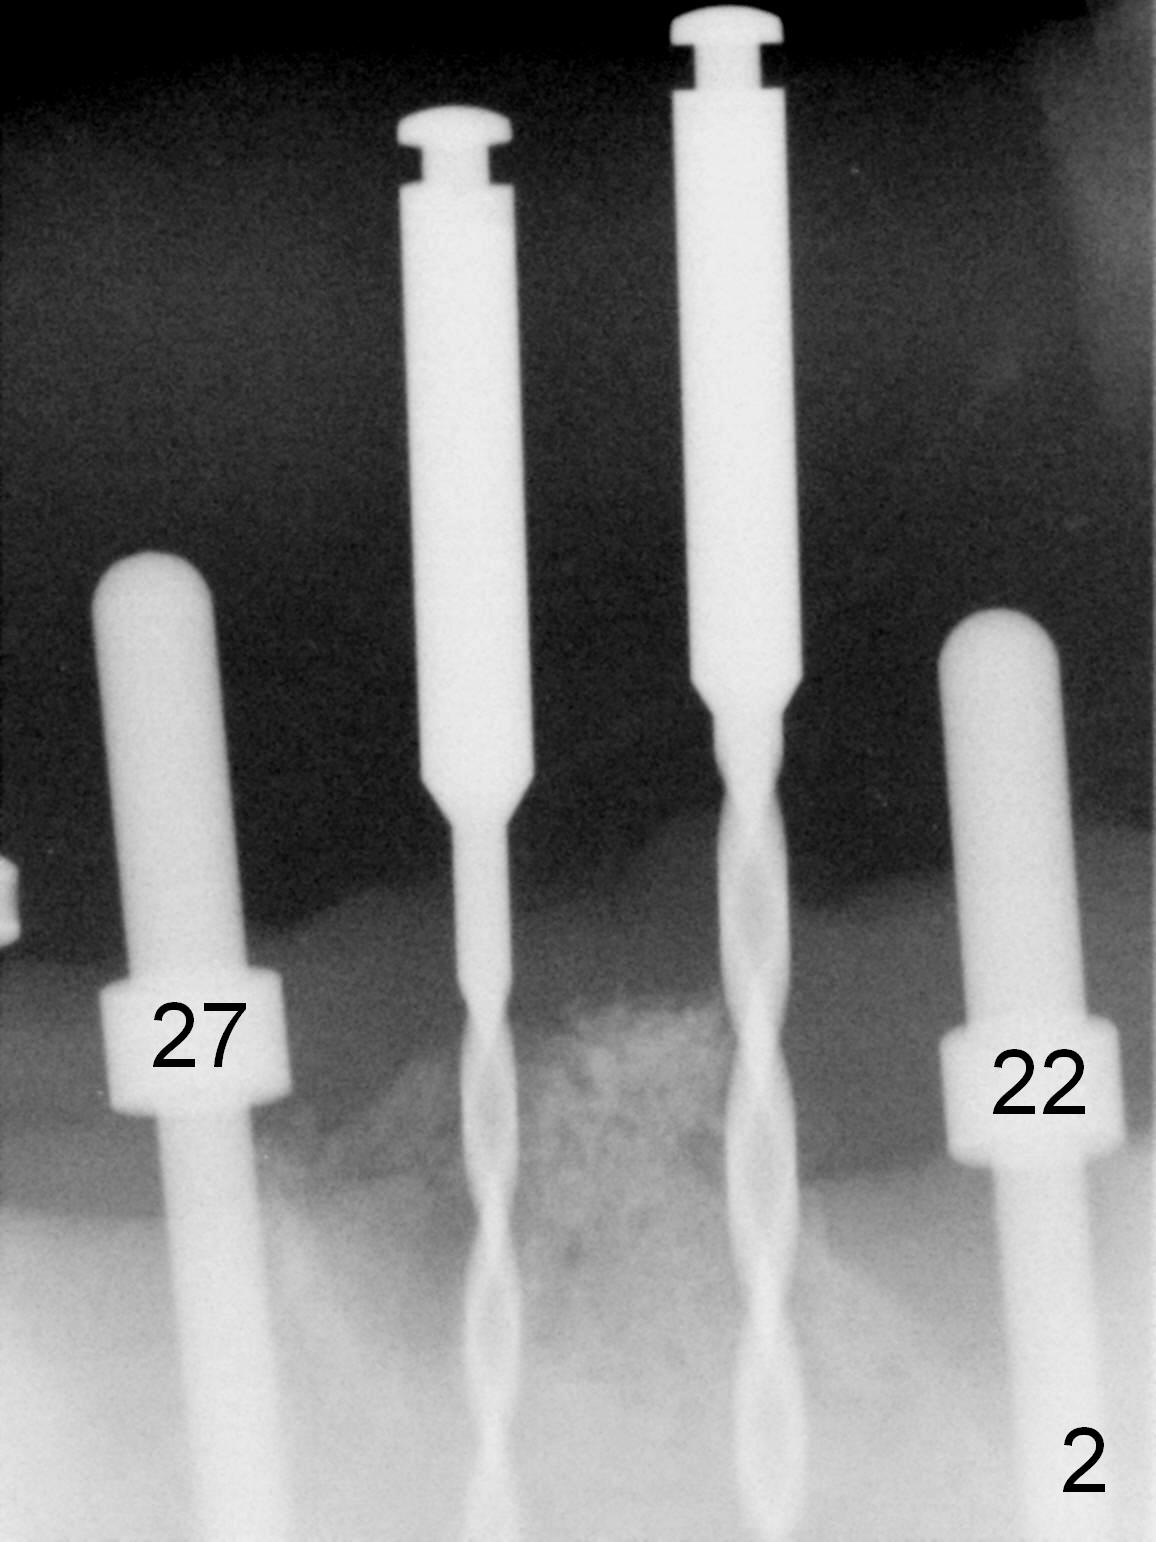

As expected, the bone density in the mandibular anterior region is found to be high during initial osteotomy (Fig.1-3).  Five implants are placed at the sites between #22 and 28 (Fig.4,5): 3x14(2) mm 1-piece (bone-level) implants in the incisor region; 4.5x17 mm 2-piece (tissue-level) ones in the canine/premolar area.  All of the implants are placed as lingual as possible.  Bone graft is placed (*).  Red dashed line: the superior border of the Inferior Alveolar Canal.  Immediate splinted provisional bridge is fabricated.  One week postop, periodontal dressing remains attached to the provisional and the gingiva.